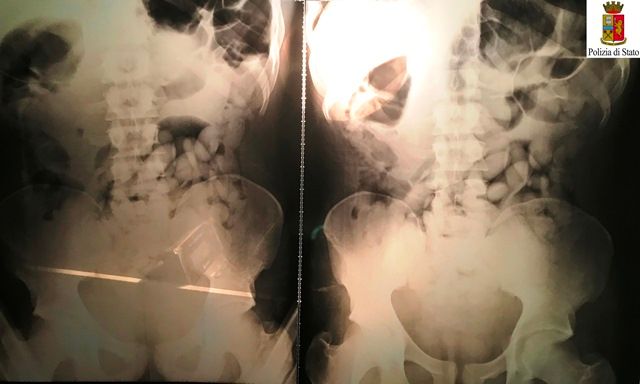

Arrestati tre "body stuffer" a Torino: avevano ingerito involucri di stupefacente

Secondo la polizia, ingoiare ovuli per sottrarsi all'arresto è una pratica sempre più diffusa nelle zone della movida